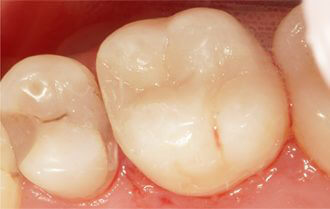

Probleem. Hambakaariese tekitatud kahjustused

Lahendus. Kaariese kahjustuste taastamine komposiittäidetega.